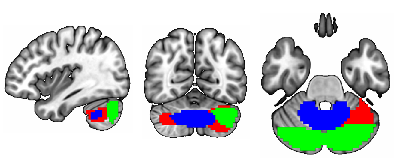

To identify the top ROIs for the intelligence prediction tasks, we first extracted the pooled ROIs after passing through the first layer of TopK Pool layer of a fully trained model using a holdout test set. We then selected the ROIs with highest frequency across each of the samples for all the intelligence scores. For fluid intelligence, we selected two ROIs (Middle Temporal Gyrus, and Middle Frontal Gyrus) (Fig 2(a)) with 90% frequency threshold. Similarly, for crystallized intelligence, middle frontal gyrus and caudate were selected with a frequency threshold of 90% (Fig 2(b)). For total composite scores, as the pooling ratio from hyper-parameter tuning was higher (0.78), we were able to extract 21 brain regions for 95% frequency. We categorized the selected regions into seven connectivity networks and plotted them independently in Fig. 3.

Refer to caption

(a) Middle frontal gyrus and Middle temporal gyrus

(b) Middle frontal gyrus and Caudate

Figure 2: Regions Significant in Fluid and Crystallized Intelligence Prediction

The top two regions contributing to fluid intelligence are the middle frontal gyrus and the middle temporal gyrus. In fact middle frontal gyrus contributes to all three intelligence scores, and its overall significance in predicting intelligence is in line with the literature. In particular, the dorsolateral prefrontal cortex in the middle frontal gyrus is well known to play a crucial part in many domains of cognitive processes, including working memory (Barbey et al. (2013)), attention control (Knight et al. (2020)), executive function (Nejati et al. (2021)), and decision making (Patterson et al. (2007)), etc (Yu et al. (2022)). Given its multi-domain involvement in cognition, this region’s engagement substantiates its relevance in all intelligence scores. The function of the middle temporal gyrus is relatively more specific to language relevant (Turken and Dronkers (2011)), such as semantic processing (Binder et al. (2009)), syntactic comprehension (Yu et al. (2022)), language comprehension, decoding intelligible speech. Its role in fluid intelligence prediction could be attributed to its contribution to information decoding and integration. In the context of crystallized intelligence, besides the middle frontal gyrus, caudate plays the most remarked contribution. The caudate’s association with learning (Choi et al. (2020)) and memory consolidation (Müller et al. (2017)) aligns with crystallized intelligence’s reliance on acquired knowledge and experience (Grazioplene et al. (2014)). The combined involvement of middle frontal gyrus and caudate suggests a cooperative engagement in translating stored knowledge into practical problem-solving skills, a hallmark of crystallized intelligence.